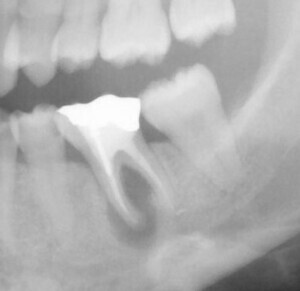

歯周病が進行し、グラグラして物が嚙めず、抜歯してインプラントにしていくことに。

インプラントはストローマンを使用、上部構造はジルコニアセラミックス